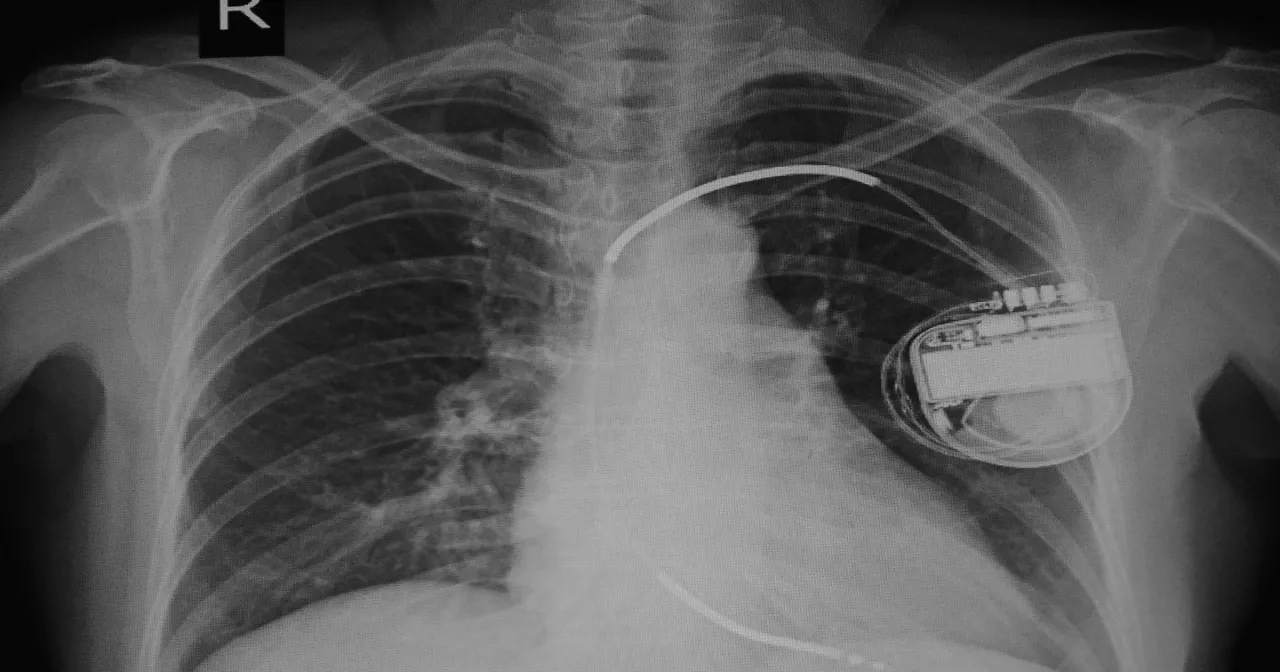

Kardiowerter-defibrylator (ICD) to zaawansowane urządzenie, które ma na celu monitorowanie rytmu serca i automatyczne reagowanie na wszelkie nieprawidłowości. Wszczepiane pod skórę, najczęściej poniżej lewego obojczyka, urządzenie to działa w sposób ciągły, analizując sygnały elektryczne płynące z serca. Gdy wykryje nieprawidłowy rytm, podejmuje odpowiednie działania, co może znacząco zmniejszyć ryzyko nagłych zgonów sercowych.

W skład kardiowertera-defibrylatora wchodzi generator impulsów oraz elektrody, które są wprowadzane przez żyły do serca. Generator impulsów, wielkości zbliżonej do pudełka zapałek, jest odpowiedzialny za dostarczanie elektrycznych impulsów do serca, gdy zajdzie taka potrzeba. Dzięki tym funkcjom, kardiowerter-defibrylator może pełnić rolę zarówno monitorującą, jak i terapeutyczną, co czyni go kluczowym elementem w leczeniu pacjentów z arytmią.